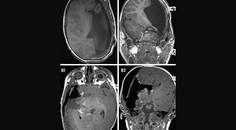

Challenge Case Report: New Onset Seizures

Ashir Bansal, BA; Matthew Tate, MD, PhDAshir Bansal, BA; Matthew Tate, MD, PhD - Epilepsy & Seizures